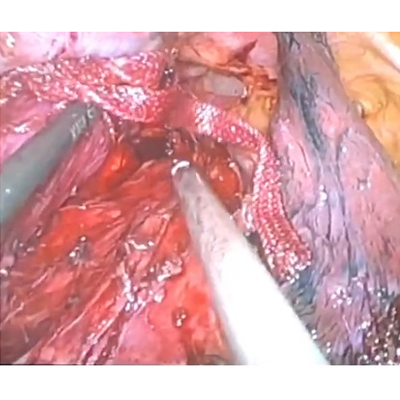

LAPAROSCOPIC WHIPPLES PROCEDURE

We have state of the art operating theatre with advanced surgical equipments. We have a Karl Storz Spies advanced HD laparoscopy operating system in addition to a 3 chip laparoscopy. We have installed advanced vessel sealing devices like Gen 11 harmonic scalpel, Ligasure from Valley Lab & Argon plasma coagulator. There is a recent addition of Cavitron Ultrasonic Aspirator (CUSA) system into our surgical armamentarium. We have the most recent powered Echelon endo-stapling devices. In addition to all these we have a constant supply of various types of advanced stapling devices for GI surgeries. Our endoscopy machines are having high definition with FICE Technology. Last but not the least we have semi flexible Ureteroscopy for managing common bile duct stones.